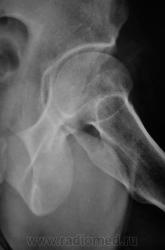

Наряду с очагом в головке, видится мне ещё и перелом - линейное нарушение кортикального слоя. И ещё очаг в крыле подвздошной кости (но может и придираюсь). Я бы взял изначально на МРТ таза и тазобедренных суставов.

С учётом того, что у нас в ЦРБ нет "высоких лучевых технологий", мы ограничились "линейкой".

1.pc160007.jpg2.pc160008.jpg3.pc160009.jpg4.pc160010.jpg5.pc160011.jpg6.pc160012.jpg7.pc160013.jpg